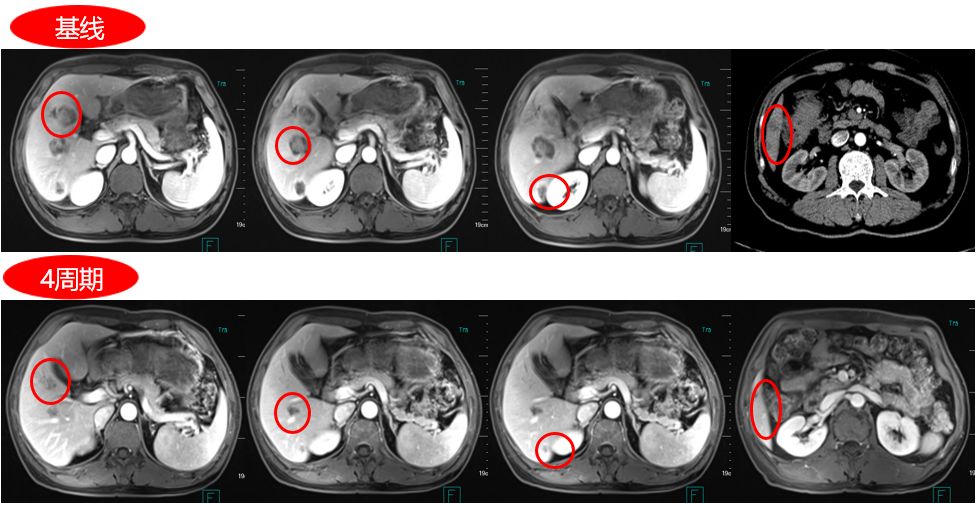

结肠癌伴多发性肝转移转化治疗病例

图片尺寸2259x1080